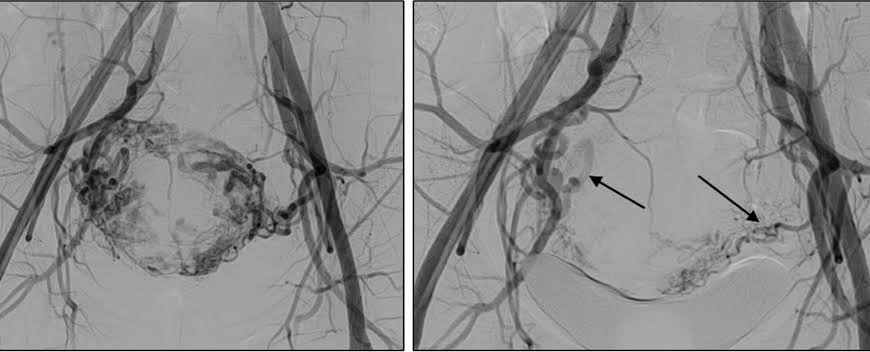

A small puncture is made to gain access to the artery, and a thin catheter is passed into the uterus to reach the uterine arteries under real-time imaging. Finally, small particles, which are aptly compared to sand grains in size, are infused to occlude smaller arteries supplying the fibroids. The particles will be lodged in these arteries and cause a reduction in blood flow to the fibroids, causing them to shrink.

Following the decrease in blood flow, there’s a gradual shrinkage in size of the fibroids. Additionally, symptoms also improve slowly. For instance, symptoms such as heavy flow might improve faster compared to symptoms such as bulk.

Both uterine arteries are usually handled through the same access point. This favors the simultaneous treatment of many fibroids.